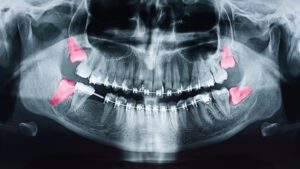

When the Orthodontist in West Orange Recommends Wisdom Teeth Removal

When the Orthodontist in West Orange Recommends Wisdom Teeth Removal How Does Wisdom Teeth Extraction Overlap With Orthodontics? When you think about getting braces or